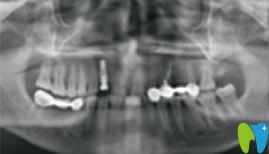

到后,我拍了一張牙齒的全景CT ,醫(yī)生建議我做種植牙。因?yàn)榉N植牙技術(shù)提取的是自體骨骼組織,與種植體完美融合。該技術(shù)適應(yīng)于所有缺牙患者,并且萬(wàn)翔口腔種植牙手術(shù)設(shè)計(jì)過(guò)程完全“可視”,治療過(guò)程微創(chuàng)、精準(zhǔn)、快速、安全,種植后的牙齒可以媲美真牙,效果也很長(zhǎng)久。